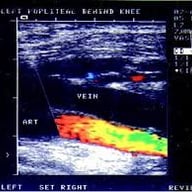

Médico Especialista em Diagnóstico por Imagem

Sou médico especialista em diagnóstico por imagem, com mais de duas décadas de experiência e atuação direcionada à ultrassonografia vascular na prática clínica.

Minha atuação é focada não apenas na execução do exame, mas na definição correta do que deve ser avaliado, como deve ser conduzido e qual é o seu real objetivo clínico.

Especialista em Doppler vascular aplicado à realidade de clínicas e serviços médicos — com foco em qualidade diagnóstica, padronização e viabilidade econômica.